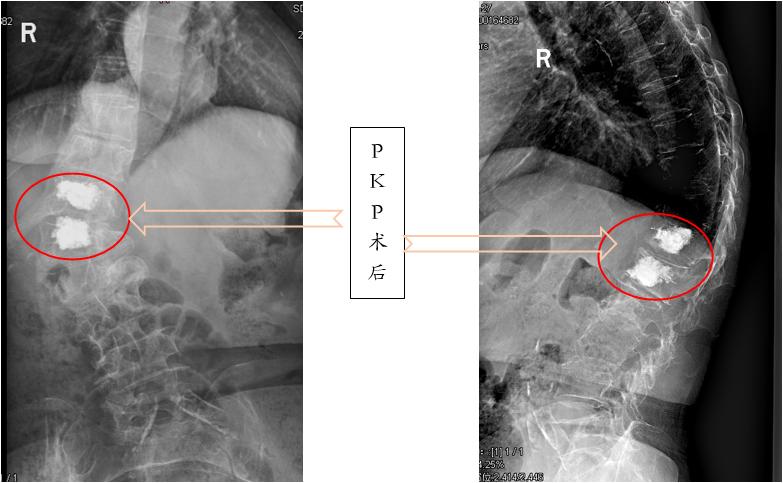

经皮椎体后凸成形术(PKP) :主要适用于出现后凸畸形的患者,在经皮椎体成形术的基础上,先将球囊输送到塌陷的椎体,将椎体撑高,再注入骨水泥。这样有助于椎体高度的恢复,矫正后凸畸形。